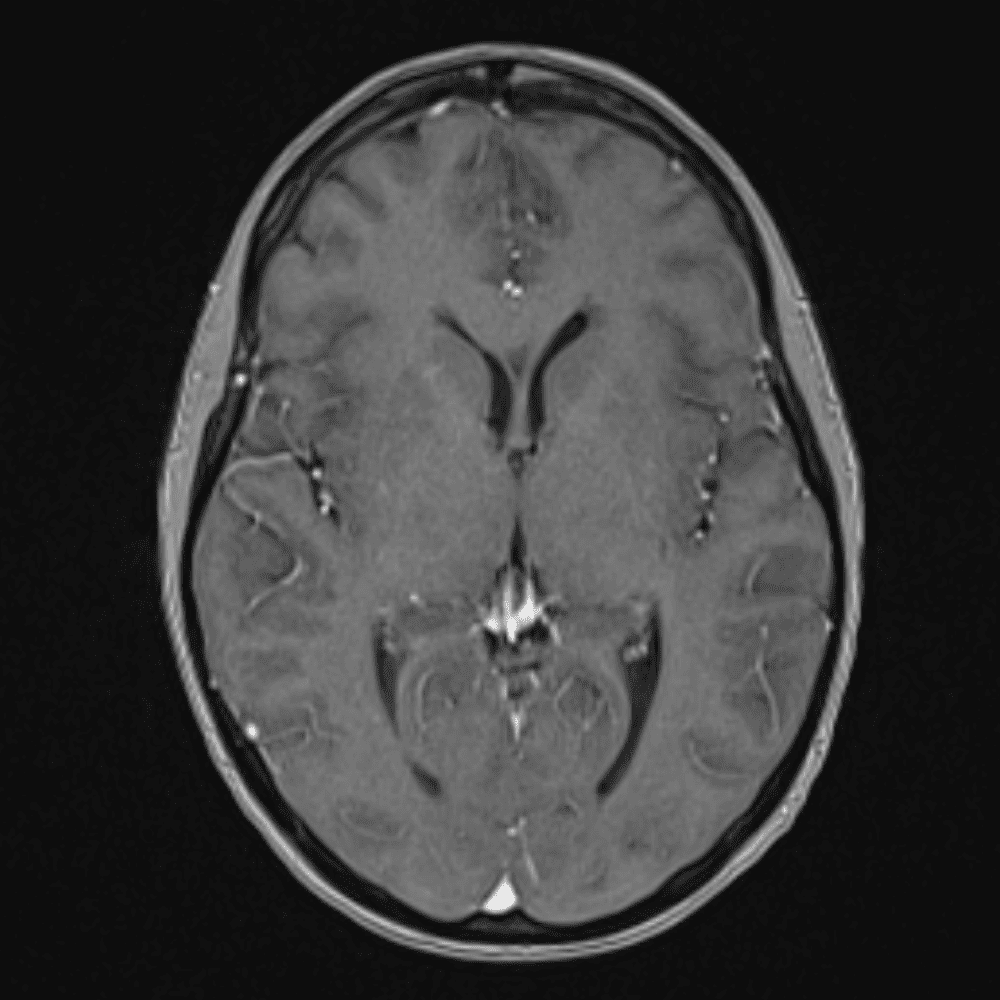

์—ฐ์Šต

๋ฏธ๋ฌ˜ํ•˜๊ฑฐ๋‚˜ ์–ด๋ ค์šด ์‚ฌ๋ก€์™€ ์ผ๋ถ€ ์ •์ƒ ์‚ฌ๋ก€๋ฅผ ํฌํ•จํ•˜์—ฌ ๋‹น์ง์„ ์‹œ๋ฎฌ๋ ˆ์ด์…˜ํ•ฉ๋‹ˆ๋‹ค.

50 ์‚ฌ๋ก€